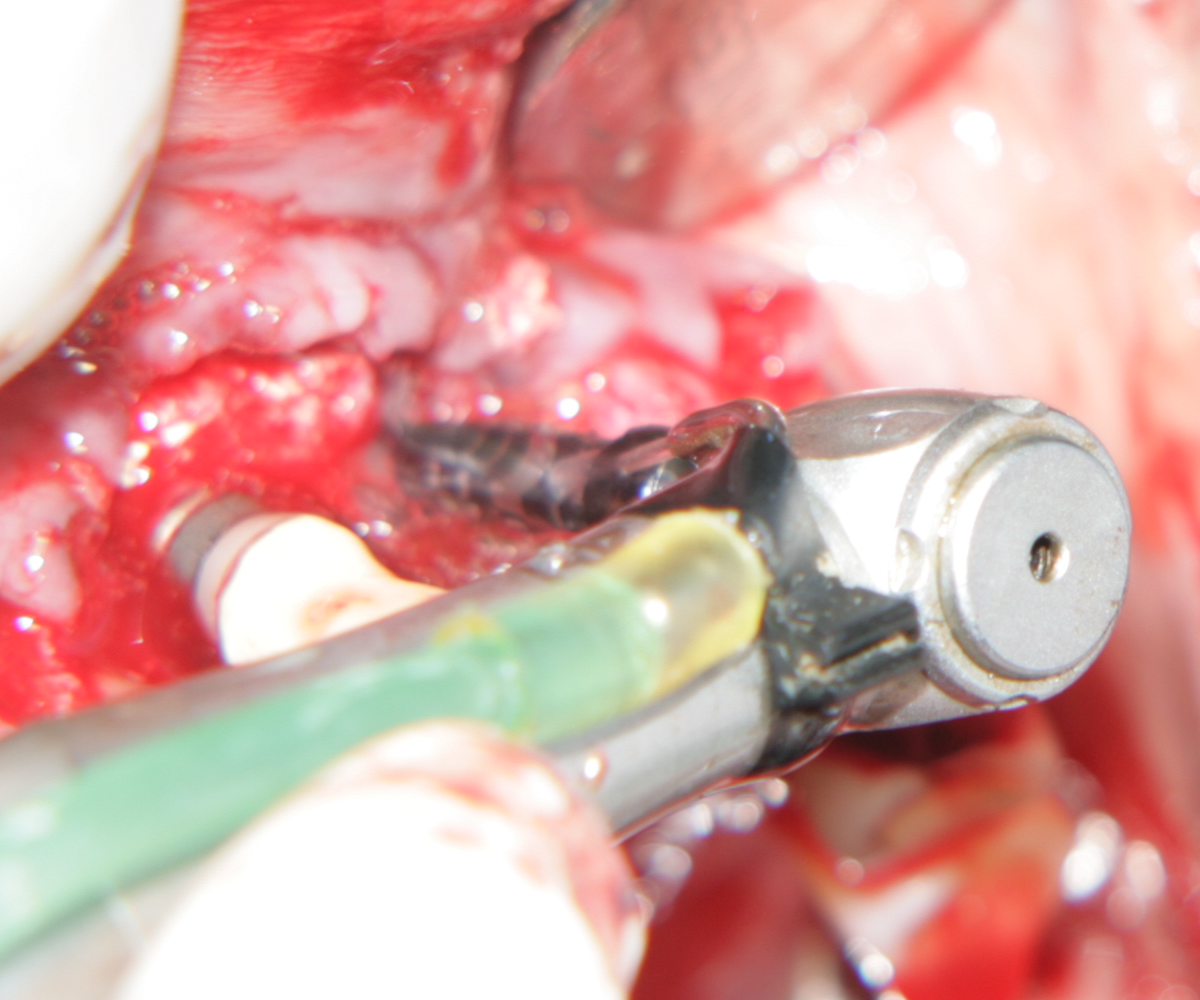

При операции с цел изграждане на допълнителн костна тъкан (костна пластика) винаги е добре да се перфорира кортикалната пластинка на костта. През тези перфорации излизат костни клетки, които постепенно прорастват в котозаместващия материал и синтезират нова костна тъкан. Перфорациите могат да се извършат с кръгло борче или с АСМ - фрезата на Neobiotech - Южна Корея.

С фрезата за автогенна кост се извършва много бързо и лесно отнемане на

кортикалната кост

Автогенна кост